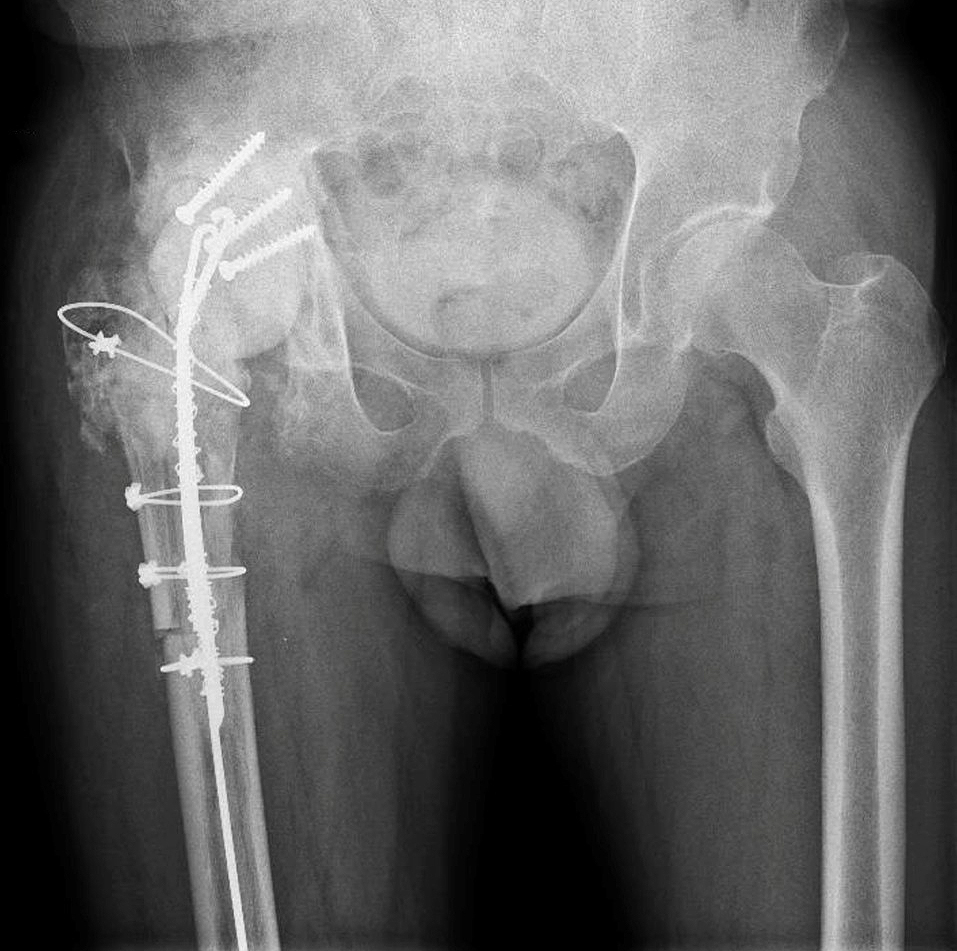

First-stage reconstruction with antibiotic-loaded spacer and temporary posterior wall reconstruction (tectoplasty) using bone cement reinforced with screw fixation.

Given the presence of a difficult-to-treat microorganism and previous failure, a repeat two-stage exchange was

indicated.

Through a posterolateral approach, implant removal was performed. Because of limited exposure and the risk of

fracturing the remaining trochanteric bone, an extended trochanteric osteotomy was required to gain adequate access to the acetabulum.

After complete implant removal, thorough surgical, mechanical, and chemical debridement was carried out.

A hand-made spacer was implanted using COPAL G+C cement. Each cement package was additionally loaded

with 2g of meropenem and 2 million IU of colistin to achieve high local antibiotic concentrations.

A particular challenge was the complete absence of the posterior wall, secondary to the old acetabular fracture. To provide containment and prevent spacer instability, a tectoplasty was performed using bone cement reinforced with three screws to reconstruct a temporary posterior wall and stabilize the spacer.

The patient underwent six weeks of targeted antibiotic therapy. After normalization of inflammatory markers and

adequate wound healing, reimplantation was scheduled.